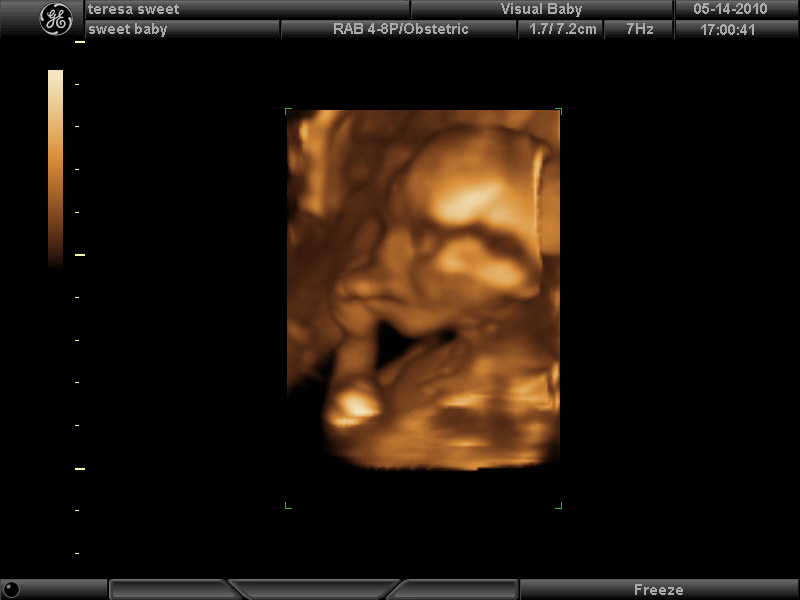

Here’s a few photos in 3D. I’m 17 wks now.